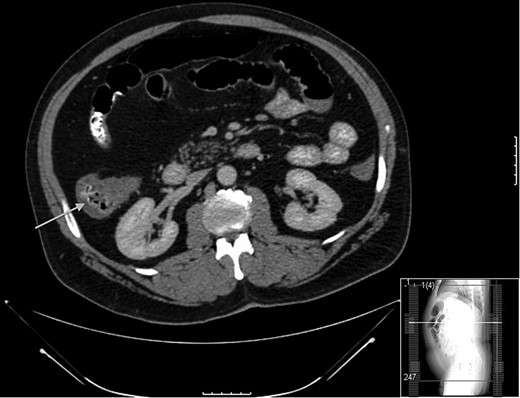

A 52-year-old male with a history of Stage IIIb melanoma initially underwent a wide local excision with a sentinel lymph node biopsy for a 2.1 mm in-depth melanotic lesion of his left upper arm melanoma. The sentinel lymph node biopsy at that time was negative for malignancy. Two years later he returned with an in-transit metastasis proximal to the original lesion. He underwent re-excision and axillary lymph dissection at that time. Following the removal of this lesion he was started on ipilimumab at 6 mg/kg. He had completed two injections spaced 1 month apart before he returning to clinic with complaints of diarrhea and significant abdominal pain. At that time a CT scan (Fig. 1) and colonoscopy with biopsy were performed, both were consistent with active colitis. Adjuvant therapy was suspended and the patient was started on prednisone at standard dosage. The patient’s symptoms improved over the course of the next week. However, 2 weeks following initiation of immunosuppresion he presented acutely to the emergency department with hypotension, peritonitis and free air beneath the diaphragm. He was taken to the operating room for exploratory laparotomy. Following entrance to the abdomen via a midline incision extensive inflammation was noted from the terminal ileum to the mid-transverse colon. Perforation of the cecum was the salient finding (Fig. 2). A right extended hemicolectomy was performed with end ileosotomy. Pathology was consistent with ipilimumab-induced perforation colitis (Fig. 3). The patient tolerated the procedure and was cared for in the surgical intensive care unit overnight before being released to the general surgery floor in the morning. His postoperative course was complicated by continued symptomatic enteritis for the next 2 weeks; however by Week 3 repeat colonoscopy revealed evidence of regeneration and healing of the colonic mucosa. He was discharged home and will likely be scheduled for ileostomy takedown in 6–8 weeks following cessation of immunosuppression.

Thickening observed on CT scan at the time of initial presentation. Note the arrow pointing to cecum on axial section.